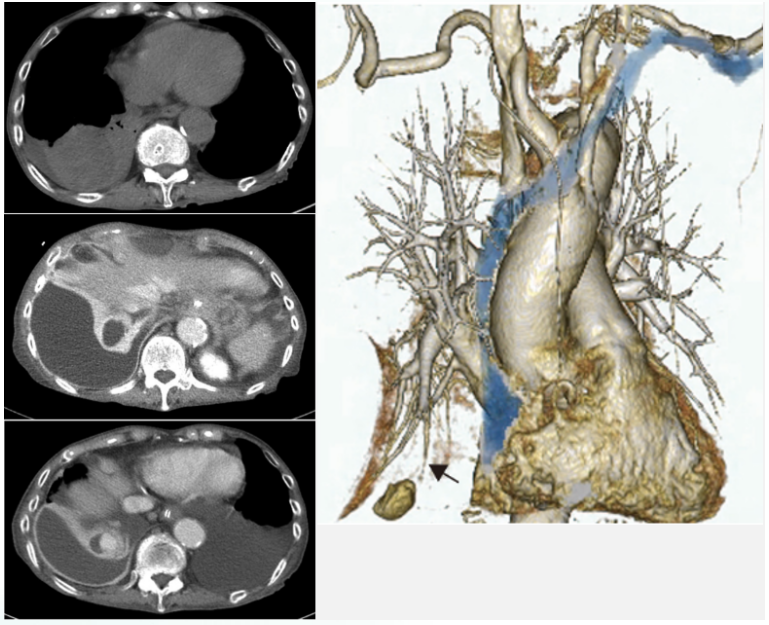

2015年Tokai J Exp Clin Med 杂志发表的文献报道了一例65岁鼻咽癌患者因肺脓肿引起肺假性动脉瘤(图19),经手术治疗后康复。

图片

19  文献报道肺脓肿引起的肺假性动脉瘤患者的胸部CT和三维重建

图源:Tokai J Exp Clin Med, 2015, 40(3):86-89.